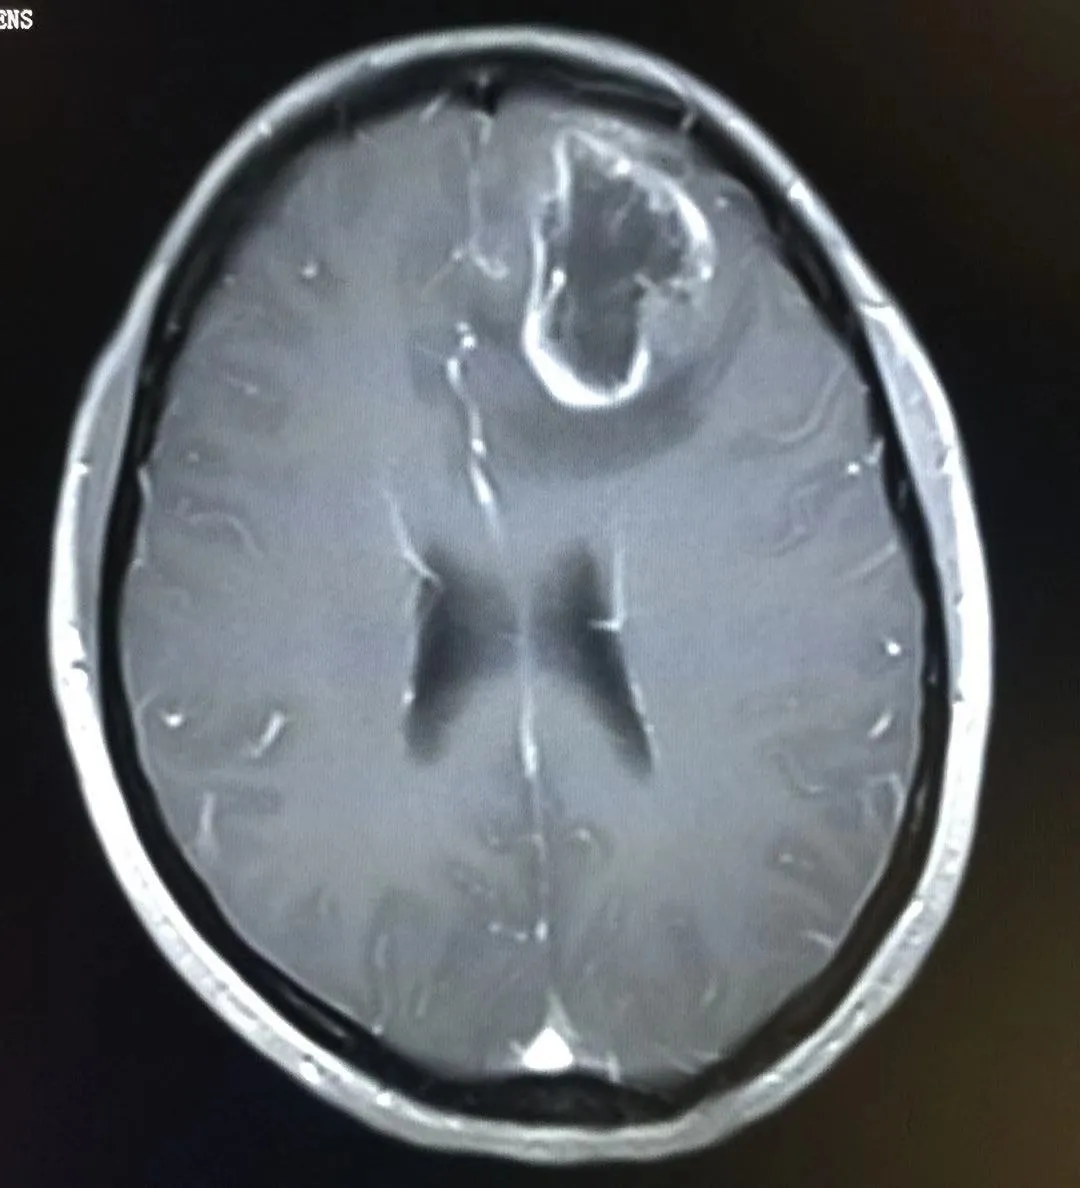

高级别胶质瘤

非脑干高级别胶质瘤的特征性磁共振成像表现包括T1加权像低信号、T2加权像皮质和白质高信号(表现为肿瘤浸润和血管源性水肿)以及不规则的强化。弥漫性内生性桥脑胶质瘤通常表现为一个大的、扩张性脑干肿块,中心位于脑桥,占据其三分之二。病变通常在T1加权像上呈低信号或等信号,边缘模糊不清,在T2加权图像上呈模糊的高信号,这反映了肿瘤的浸润性。但在液体衰减反转恢复序列图像上,弥漫性内生性桥脑胶质瘤经常显得相对均匀。这些肿瘤的对比增强可能是可变的,但无明确的预后意义。

大脑脑叶高级别胶质瘤

儿童大脑半球高级别胶质瘤的手术与基于术中影像的导航密切相关,尤其对于“功能区”或“功能哑区”的肿瘤定位,这与总体生存率相关。外科干预的目的是获取组织以进行组织学诊断和实现肿瘤减容。边界清晰的病灶可通过肿瘤全切治疗,而浸润性较强、边界不明显、侵犯中线或涉及脑深部结构的肿瘤,手术的目标应该是安全的最大程度切除。